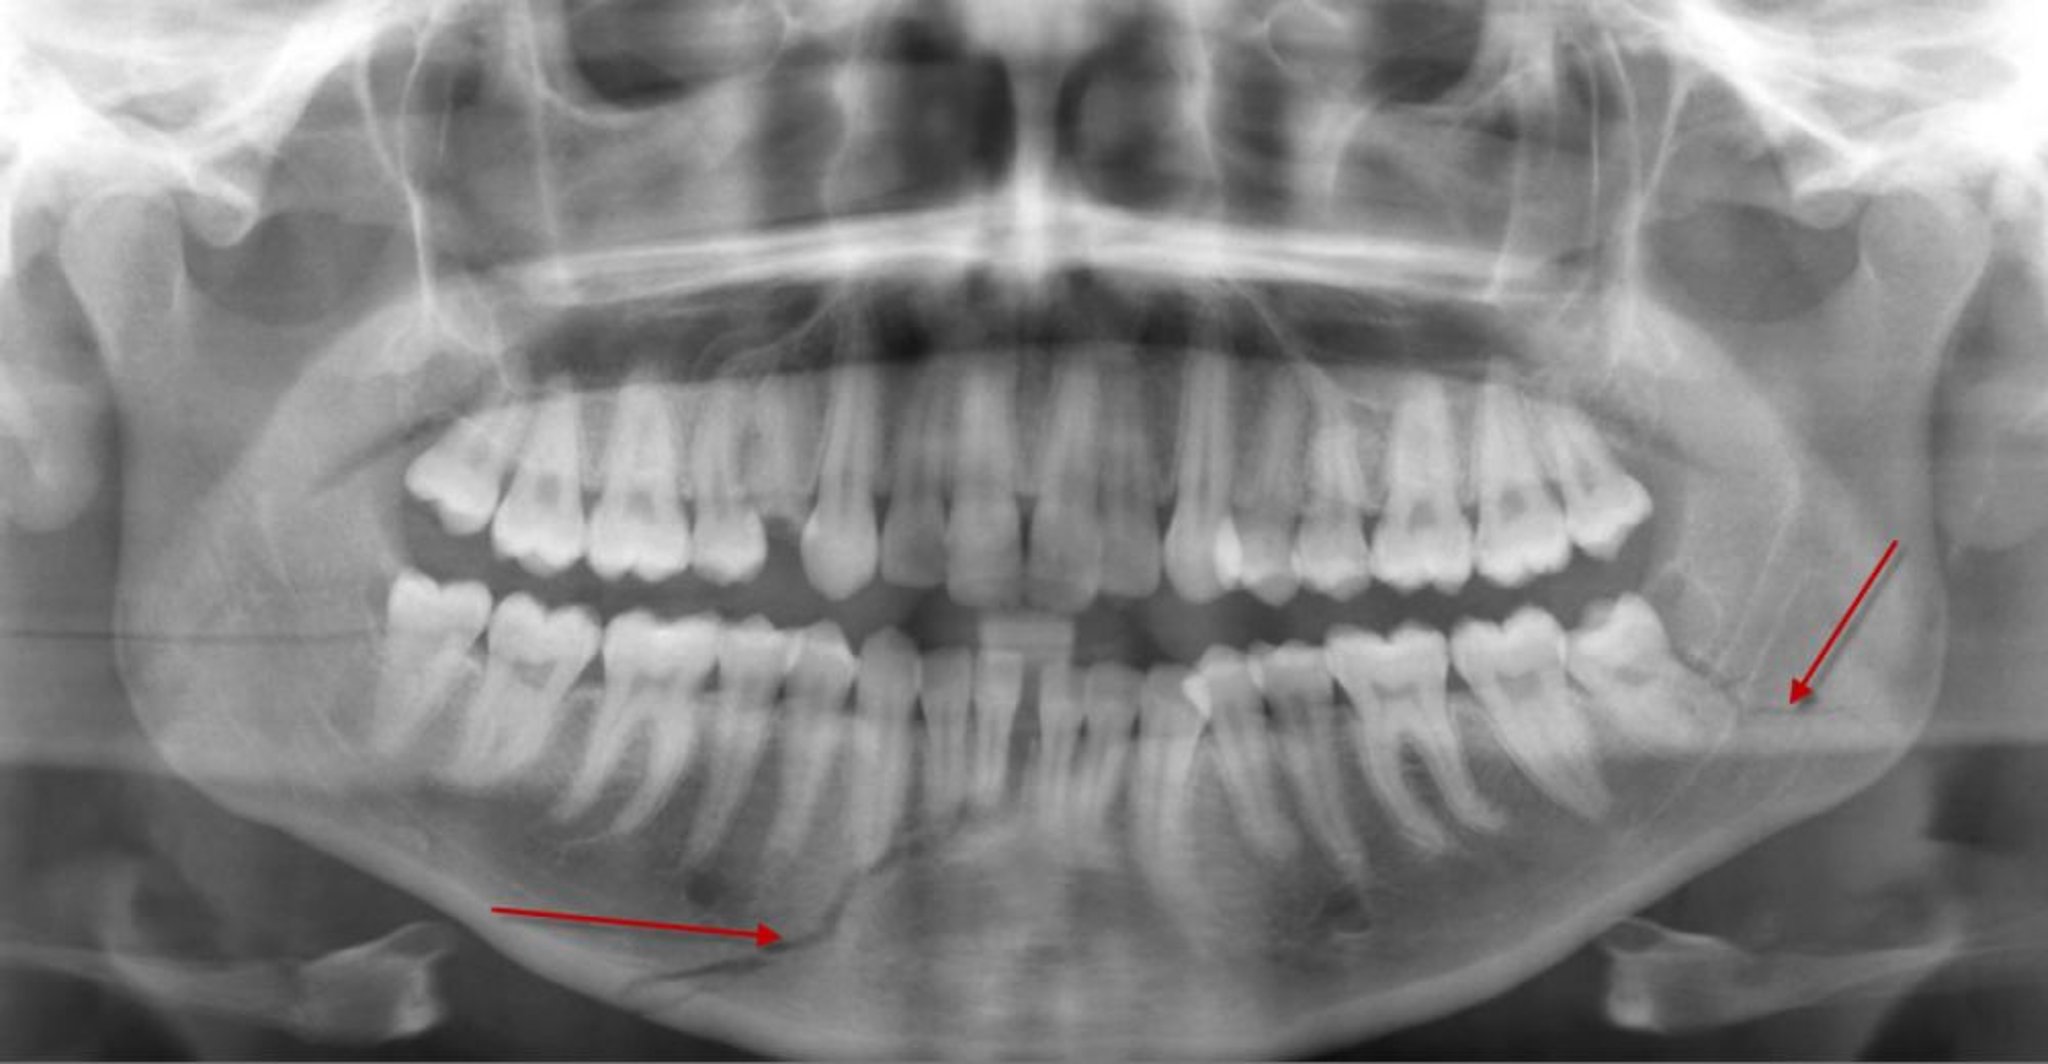

Fractura del cuerpo mandibular

Esta radiografía panorámica muestra una lucencia (flecha inferior) en el cuerpo de la mandíbula, compatible con una fractura, que llega a las raíces de algunos dientes anteriores inferiores. También hay una fractura del ángulo mandibular izquierdo (flecha).